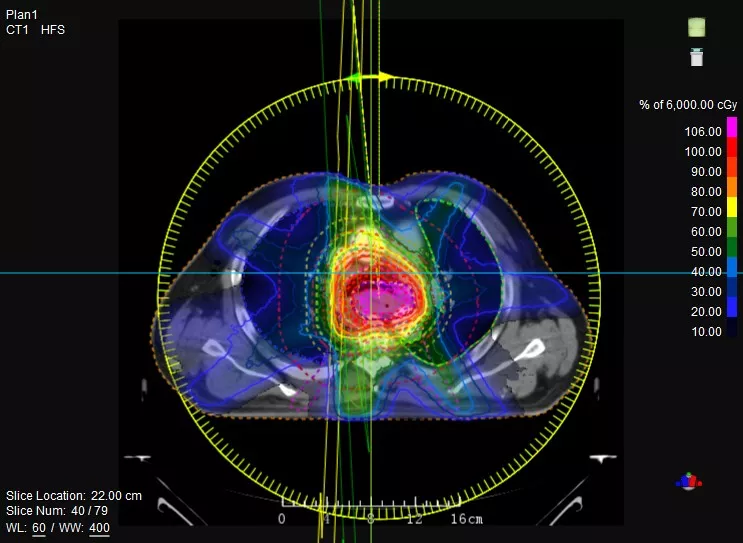

觀其“外在”——首創(chuàng)Linac與CT真正一體化融合,精準CT模擬定位、高清CT影像引導(dǎo),實現(xiàn)精準高效的放射治療。

究其“內(nèi)在”——聯(lián)影自主研發(fā)高劑量率加速管、動態(tài)精準多葉光柵、蒙特卡羅金標準劑量算法、智能勾畫等核心部件與技術(shù),確保系統(tǒng)高兼容性及設(shè)備高效性。

動態(tài)精準多葉光柵,120葉鎢合金葉片,等中心葉片寬度最薄5mm,支持動態(tài)治療

TPS集成蒙特卡羅、三維卷積劑量算法和智能勾畫等功能

一款設(shè)備即可滿足CT模擬定位、CT影像引導(dǎo)、uARC動態(tài)旋轉(zhuǎn)調(diào)強放療等重要臨床應(yīng)用,無需科室/治療室間切換,一站完成放療全流程。

機載CT影像可直接用于放療計劃制作